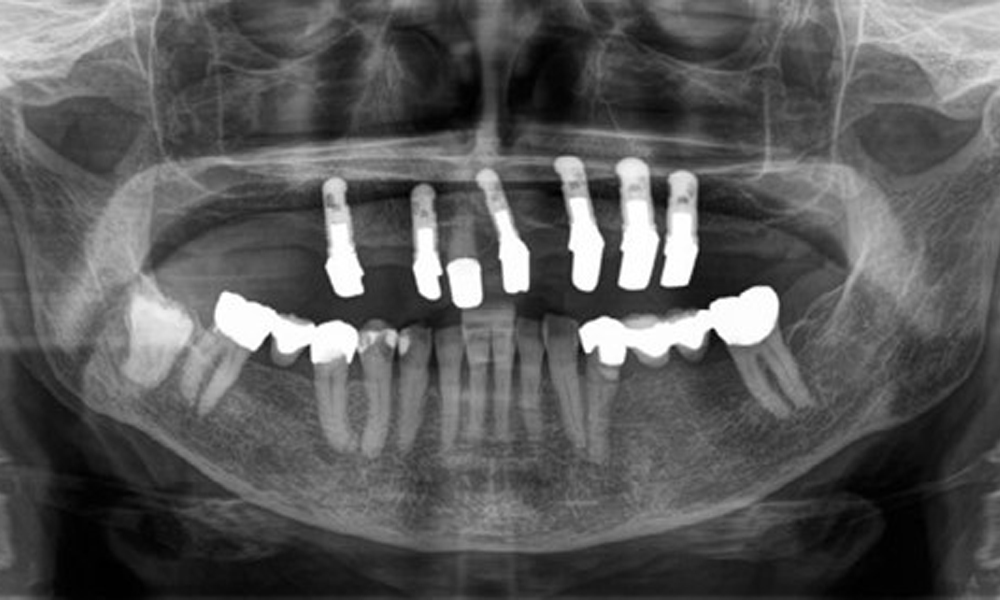

Der dentale Befund stellt sich wie folgt dar: Kombinierte herausnehmbare Implantat- und zahngetragene Teleskoparbeit auf Implantaten 15, 13, 21, 23, 24, 25 und Zahn 11 (Abb. 1, Abb. 2, Abb. 3). Im Unterkiefer ist die Patientin mit einem festsitzenden Zahnersatz versorgt. 37–34 sowie 45–47 haben suffiziente Brücken (Abb. 4). Kronenränder sind intakt, aktive kariöse Läsionen sind nicht vorhanden. An Zahn 43 zeigt sich eine Compositefüllung mit Randspalt. Im Unterkiefer liegen Rezessionen mit freiliegender Wurzeloberfläche zwischen 1 – 3 mm vor. Dies trifft auch für 11 zu.

Aus dem radiologischen Befund zeigt sich ein teilbezahntes Gebiss mit Implantaten im Oberkiefer an 15, 13, 21, 23, 24, 25 und einer Teleskopkrone 11. Im Unterkiefer sind suffiziente Brücken von 37–34 und 45–47 vorhanden. 48 ist retiniert. 43 distal besteht der Verdacht auf Sekundärkaries und 44 mesial Verdacht auf Sekundärkaries. 44 ist mit einer nicht röntgenopaken Unterfüllung versorgt.

Es zeigt sich ein generalisierter horizontaler Knochenabbau von ca. 10–30 % und lokalisiertem vertikalen Knochenverlust an 22 und 42. (Abb. 5)